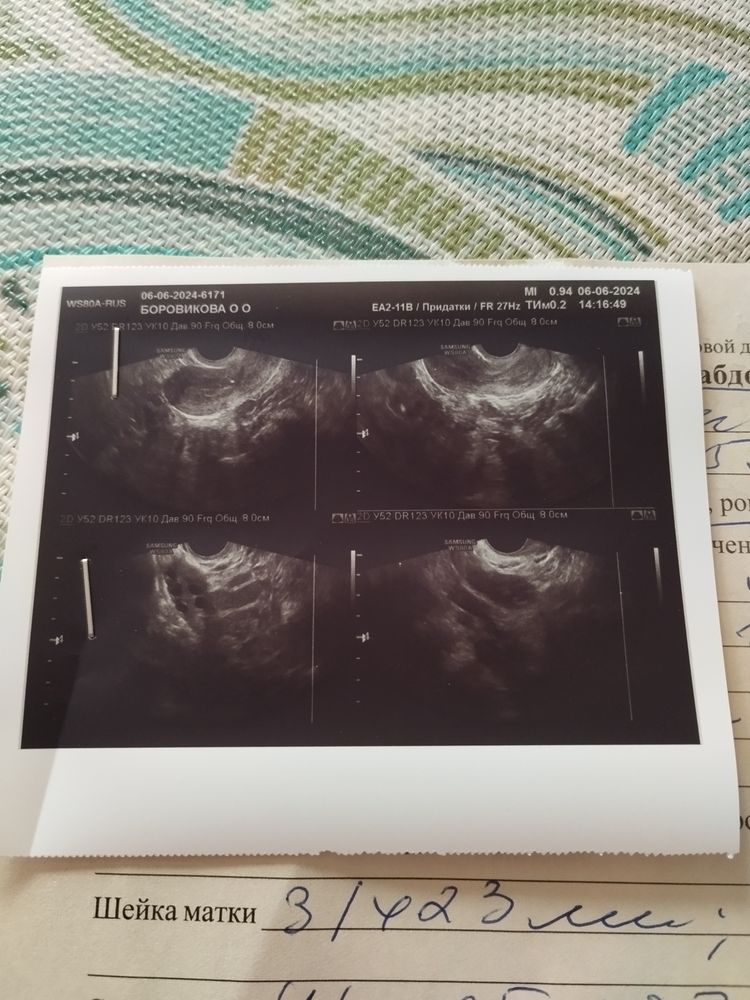

Ольга Боровикова, Не может быть такого)Последняя фаза цикла 14-16 дней! И эндометрий у вас всего 7мм ,а после овуляции он от 10мм.Узи платно делали?